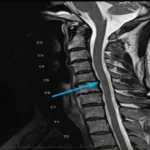

Angio Brain/Neck is a medical imaging test that uses advanced technology to visualize the blood vessels in the brain and neck. This non-invasive diagnostic test is used to diagnose various medical conditions such as stroke, aneurysm, and arteriovenous malformations (AVMs) that affect the blood vessels in the brain or neck.

The test is usually performed using a CT or MRI machine, which uses a powerful magnetic field and radio waves to create detailed images of the blood vessels in the brain and neck. During the test, the patient will lie down on a table that slides into the machine. The machine will then take multiple images of the brain and neck, which will be analyzed by a radiologist or a neurologist.

The results of the Angio Brain/Neck test are interpreted by a radiologist or a neurologist. The images may show abnormalities in the blood vessels, such as narrowing, blockages, or bulging, that may indicate a medical condition, such as an aneurysm or stroke. Depending on the severity of the findings, the healthcare provider may recommend further testing or treatment, such as medication, surgery, or lifestyle changes.